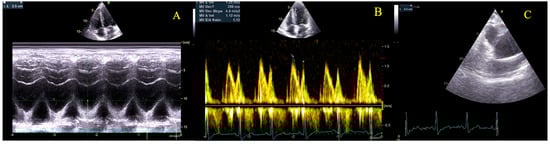

| Gestational Age (Weeks) | Heart Rate (bpm) | Hb (g/dL) | NT-proBNP (pg/mL) | 6mWT (m) | LVEF (%) | LVOT VTI (cm) | AV VTI (cm) | Maximum AV Gradient (mmHg) | Mean AV Gradient (mmHg) | Indexed Aortic Valve Area (cm2/m2) |

|---|---|---|---|---|---|---|---|---|---|---|

| 22 | 76 | 11.5 | 45 | 670 | 59 | 27.5 | 99.3 | 96 | 58 | 0.475 |

| 26 | 73 | 60 | 27.3 | 99.2 | 94 | 60 | 0.475 | |||

| 29 | 82 | 11.4 | 59 | 625 | 60 | 26.9 | 99.8 | 93 | 60 | 0.463 |

| 30 | 85 | 61 | 27 | 102 | 108 | 60 | 0.457 | |||

| 31 | 81 | 60 | 26.9 | 101.8 | 95 | 58 | 0.469 | |||

| 32 | 78 | 12.1 | 67 | 630 | 59 | 27.2 | 100 | 103 | 62 | 0.469 |

| 33 | 76 | 59 | 27.5 | 99.5 | 100 | 61 | 0.475 | |||

| 34 | 84 | 61 | 27.9 | 101 | 101 | 60 | 0.475 | |||

| 35 | 82 | 12.5 | 37 | 615 | 61 | 28 | 100.6 | 95 | 55 | 0.481 |

| 36 | 80 | 60 | 26.4 | 99 | 89 | 52 | 0.463 | |||

| 37 | 85 | 12.6 | 62 | 27 | 100 | 93 | 56 | 0.469 | ||

| 38 | 86 | 12.3 | 66 | 575 | 62 | 26.5 | 99.8 | 92 | 55 | 0.457 |

| 3 months postpartum | 70 | 11.9 | 54 | 654 | 60 | 28.3 | 118 | 103 | 68 | 0.50 |